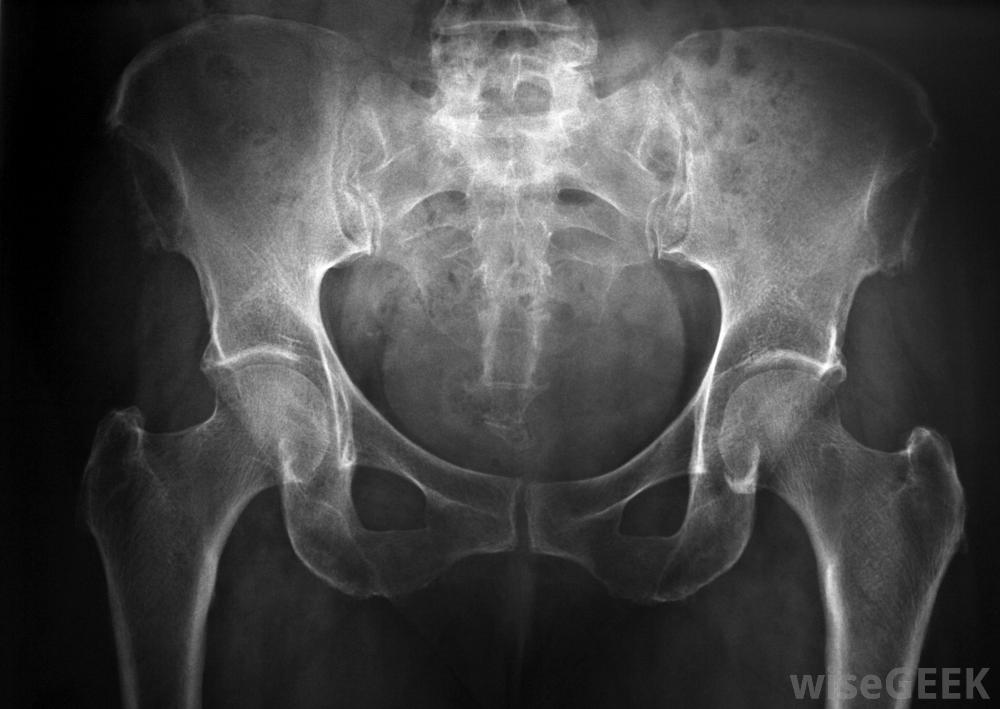

骶髂關節位于脊椎底部的一對,在這里它與骨盆骨相接。在運動中,左右關節共同承擔重量并穩定脊柱。當一個或兩個關節發炎時,一個人可能會經歷慢性下腰痛和有限的活動范圍。醫生可以通過確定潛在原因和癥狀的嚴重程度來決定如何治療骶髂關節炎。大多數人可以通過避免劇烈活動和服用消炎藥來恢復,雖然嚴重的病例可能需要手術和后續的物理治療以恢復體力和柔韌性。懷孕婦女可能會因骶髂發炎而感到疼痛骶髂關節組織的炎癥可由直接損傷、過度使用、關節炎或嚴重感染引起。一些婦女在懷孕期間由于骨盆壓力增加而出現癥狀。此外,關節發炎、關節發炎、關節發炎、關節發炎、關節發炎等癥狀也會導致關節發炎、關節發炎、關節發炎等癥狀,脊椎底部的紅色皮膚。X光片可用于診斷骶髂關節炎癥當出現背痛的第一個征兆時,與醫生交談是很重要的,這樣才能做出準確的診斷。醫生可以通過進行體格檢查、詢問癥狀和對關節進行x光檢查來診斷骶髂關節的問題。醫生調查其根本原因很重要,非甾體抗炎藥(NSAIDs)可能有助于對抗骶髂關節炎癥和疼痛在輕度病例中,如果確定原因是急性損傷或過度使用關節,醫生通常建議病人在家里治療骶髂關節炎。病人通常被要求休息幾天或幾周,避免劇烈的體力活動。冰袋可以幫助止痛消腫,外用軟膏可以緩解皮膚組織的刺激。許多病人服用非處方消炎藥來進一步減輕癥狀。當一個人遵照醫生的指示治療骶髂發炎時,癥狀往往會在兩到四周內消失骶髂關節炎癥患者通常會經歷慢性下腰痛如果患者患有關節炎或潛在的免疫系統問題,他或她可能需要服用專門的處方藥來緩解疼痛。處方中的皮質類固醇和高強度抗炎藥可以減輕疼痛并幫助減緩組織損傷的進展。醫生還告知患者可以進行哪些運動來保持骶髂關節的柔韌性嚴重的軟骨損傷和骨缺損通常對藥物沒有反應。骨科醫生可以決定通過切除或修復受損組織的過程。手術后,病人通常會被送到物理治療中心。訓練師可以幫助病人進行專門的伸展和強化訓練,從手術中恢復過來,并再次享受常規活動骶髂關節位于脊柱底部一對,在那里它與骨盆骨相交。